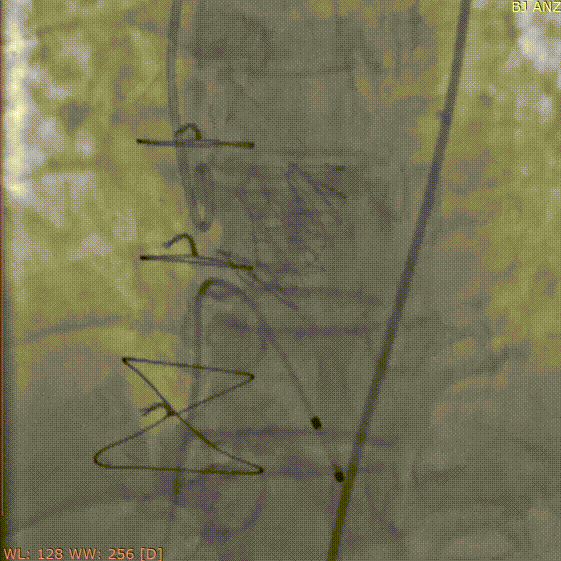

定位件入窦

释放瓣膜

手术过程和结果

术中采用局部麻醉,经股动脉穿刺建立血管通路,首先采用22mm球囊对病变部位进行预扩张,预扩时无明显腰征及反流,之后将杰成主动脉瓣输送器送入主动脉瓣目标位置,轻松实现定位件的正确入窦,后成功释放22mm瓣膜,之后采用22mm球囊进行后扩张,整个手术过程行云流水,仅用时20分钟。经DSA造影和超声等综合评估显示瓣膜释放位置完美,瓣膜工作稳定,术后即刻主动脉瓣上峰值流速:204cm/s、峰值压力阶差:16mmHg,平均压差:8mmHg,人工主动脉瓣瓣环内无反流,微量瓣周漏,患者临床症状和血流动力学明显改善。